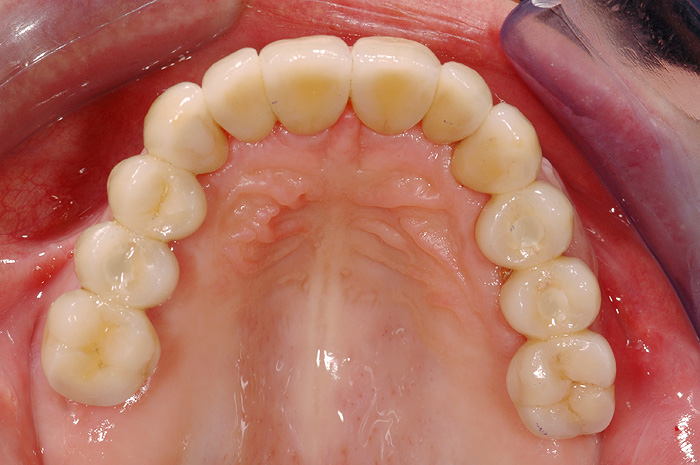

Fallbeispiel

Zum Vergrössern klicken